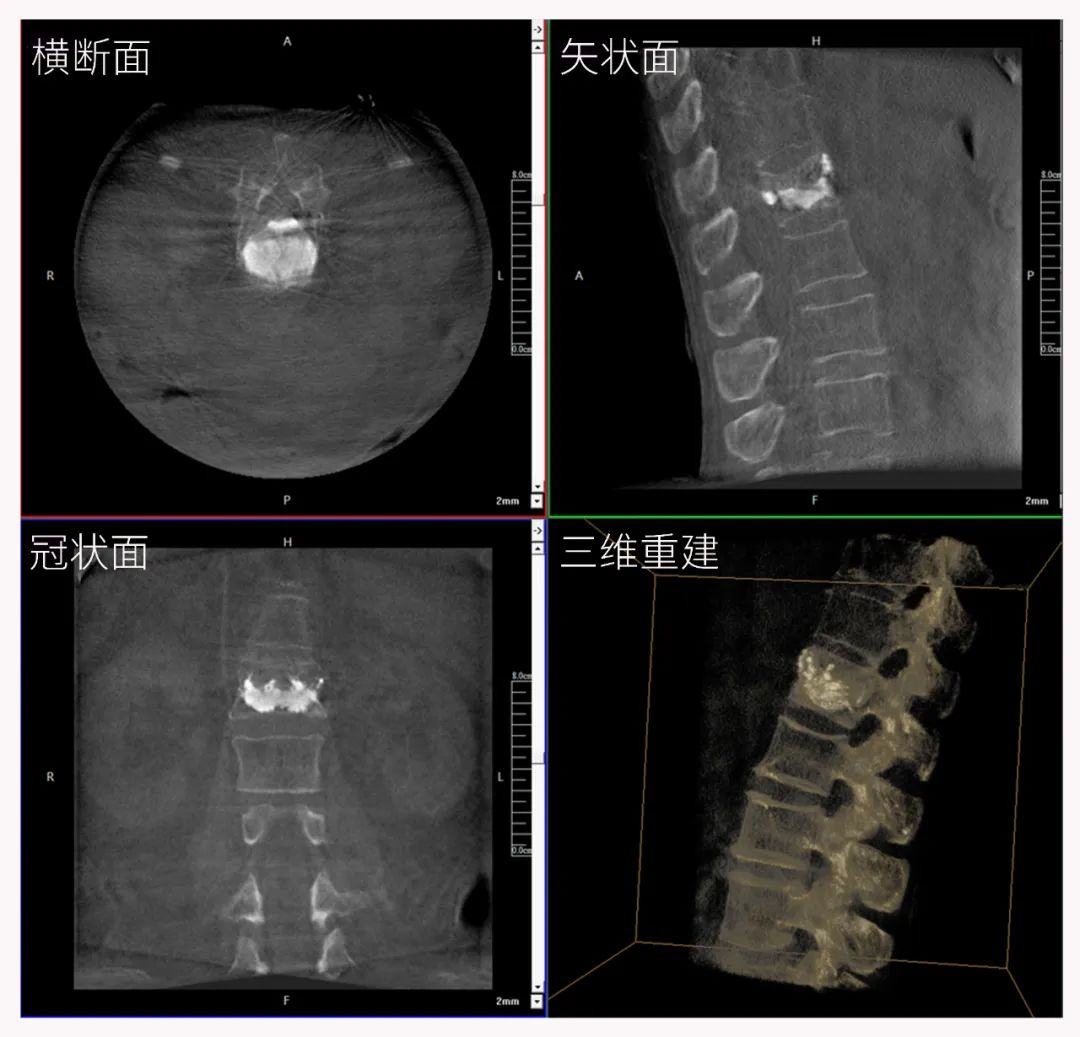

三維C形臂也被稱為“術中CT”,它具備二維C形臂的全部功能。此外,它還具備三維成像功能,三維C形臂旋轉采集多角度的二維投影數據,再通過計算機進行三維重建,能夠生成橫斷面、矢狀面、冠狀面斷層圖像以及三維立體圖像,提供更全面、更立體的解剖學信息。

三維“類CT”影像

三維切面影像可以看出病灶點